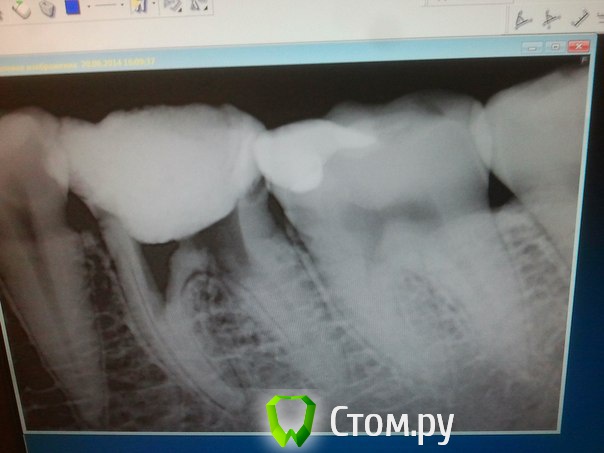

Инна Владимировна Опубликовано 25 июня, 2014 Автор Поделиться Опубликовано 25 июня, 2014 Все, товарищи, сходила. Зуб оказался как решето. Но все равно решили помучиться - залепили, залили... Врачи очень старались))) Прошло вот 5 часов, болит, конечно. И все удивились, зачем первый врач -Елонова Елена Анатольевна так издырявила зуб. Ссылка на комментарий

DokDent Опубликовано 25 июня, 2014 Поделиться Опубликовано 25 июня, 2014 Все, товарищи, сходила. Зуб оказался как решето. Но все равно решили помучиться - залепили, залили... Врачи очень старались))) Прошло вот 5 часов, болит, конечно. И все удивились, зачем первый врач -Елонова Елена Анатольевна так издырявила зуб. А снимок? Интересно глянуть 1 Ссылка на комментарий